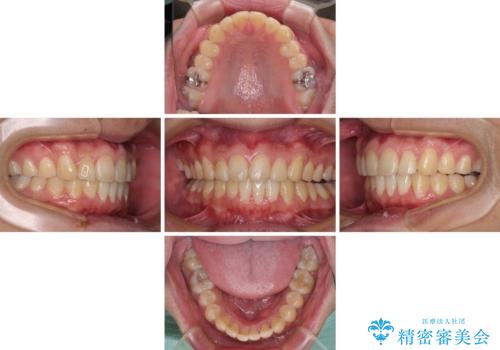

写真より左側臼歯の咬合がタイトではないことが分かりますが、こちらは保定期間に徐々に咬合させていくこととしました。